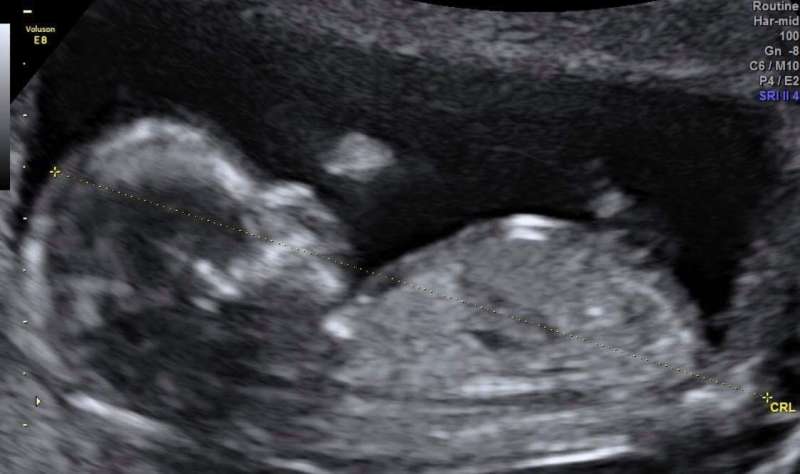

2018年05月14日台灣女歌手魏如萱日前選擇在母親節凌晨1點PO出了超音波照片,自爆35歲的自己已經未婚懷孕,而她的經紀人也向媒體表示,她已經懷孕3個月,雖然還未與隆宸翰結婚,不過目前已經朝著這個方向在規劃當中。

▼不過因為醫生告訴她屬於比較難受孕的體質,子宮的分數也低於標準,讓她有考慮過先凍卵或是尋求其他方式,最後還是決定順其自然就好。沒想到在她們沒想太多的時候,「這個美好的禮物悄悄的來了」。

▼不過已經35歲的魏如萱已經算是高齡產婦,懷孕也為她帶來了身體上的改變,「我可以強烈感覺到身體正在重組,荷爾蒙的影響會有點不舒服,有時會忽然當機進入深沉的熟睡,還有嗅覺變得更敏銳了,很想吃東西然後就胖了…之前一開始偶爾會出血的狀況不是太穩定,有打針也有吃藥,我的心情是很忐忑不安的,真的是花了一些時間才比較適應還有比較穩定,希望你們能體諒我到現在才分享這個消息。」